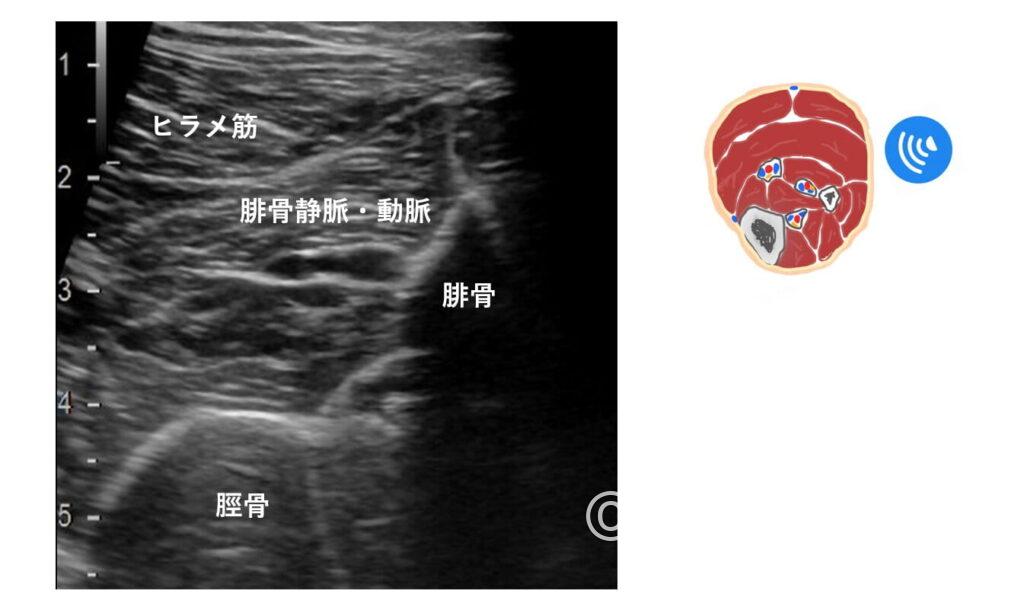

特に【後脛骨静脈】と【腓骨静脈】でしょうか。

脛骨は円弧状、腓骨は鋭角に見える(大昔に他施設さんへ研修へ伺った際、教えていただいた先生は腓骨を『富士山』と表現していました)

なので、側を走行している血管はそれぞれ後脛骨静脈(前脛骨はふくらはぎからではなく下腿前面からスキャンすれば描出できます)、腓骨静脈と考えられます。

ただ、後脛骨静脈は脛骨から少し離れているので少し難しい印象。

個人的には、ヒラメ筋内側にに沿って走行する血管は後脛骨静脈であることが多いのかなと。